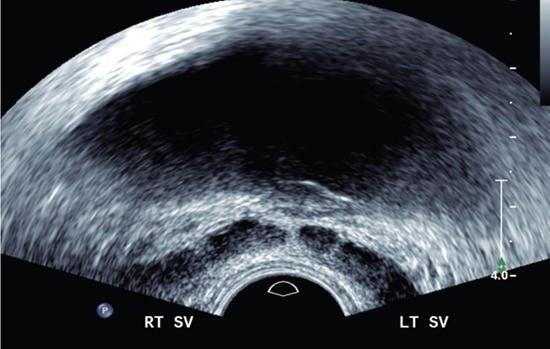

Anidudha Kulkarni Seminal vesicles (SVs) are an integral part of male genitourinary system. SVs are paired accessory gland which plays a major role in male fertility. They produce an alkaline fluid contributing 50%–80% of the ejaculate volume. Male genital organs collectively work to produce semen, consisting of mature spermatozoa. There are no specific signs and symptoms for pathologies in SVs. The common complaints include pain, recurrent UTI and dysuria. Commonly, an abnormality is identifies while investigating for an unrelated pathology such as infertility or a prostatic nodule. SVs are paired organs, measuring 5–7 cm in length, which are rounded superiorly and taper inferiorly. SVs are located posterior to the bladder and inferolateral to the vas deferens. This bilateral positioning of the SVs creates a ‘V’-shaped configuration. SVs are positioned superior to prostate. They lie at the inferior aspect of the rectovesical pouch. SV ducts merge with ampulla of vas deferens and form the ejaculatory duct which opens into the prostatic urethra at the level of verumontanum. SVs contain highly granular cells that produce straw coloured alkaline fluid containing fructose, proteins and vitamin C under the influence of testosterone. The fructose provides the required energy for the motility of spermatozoa. This fluid makes up two-thirds of the total ejaculate volume. Rest of which comes from the prostate gland, vas deferens and lesser amounts from bulbourethral and Cowper’s glands. SVs appear as fluid-filled structures, with a thin septations on contrast-enhanced CT. This modality remains helpful in recognizing many SV abnormalities. On MRI they show low signal intensity on T1-weighted and high signal intensity on T2-weighted images and appear as elongated fluid-filled structures with thin septae. SVs appear as symmetric organs which lie cephalad to the prostate and posterior to the bladder They have a typical ‘bow-tie’ appearance in transverse scans and a club or tennis-racket shape in longitudinal scan. They show homogenously fine echoes, however they are less echogenic than prostate. SV volume is positively affected by circulating testosterone and prolactin, and increases during a prolonged sexual abstinence. Volume of SVs tends to shrink after the fifth decade. SV agenesis is a rare congenital anomaly with an incidence of 0.08%, where there is a complete or partial absence of one or both SVs. This anomaly results in infertility secondary to azoospermia. Patients are generally asymptomatic. Only symptom is infertility and thin low volume ejaculate. TRUS remains the modality of choice to diagnose patients with SV agenesis. There is no treatment available for the SV agenesis. The ureteric bud develops from the mesonephric duct during the 5th week of intrauterine life. In the 7th week, the testes develop and differentiate the male genital system. SVs develop as a bulbous swelling of distal portion of mesonephric duct during the 12th week of gestation. SVs are retrovesicle to the urogenital sinus. SV agenesis is often associated with abnormal development of other mesonephric/metanephric derivatives, such as the VD, ureter and kidney. Unilateral SV agenesis is due to insult occurring before the 7th week of gestation, when the ureteric bud arises from mesonephric duct. Bilateral SV agenesis is related to CFTR gene mutations (64%–73% of cases). A decreased SV volume is defined as hypoplasia, and mainly refers to congenitally small SV, although an acquired form may be associated with testosterone deficiency or postinfective scarring. The normal SV measures >25 mm in length. They are considered to be hypoplastic when >16 mm but <25 mm and atrophic when <16 mm Another parameter which can be considered for hypoplasia is the maximum anteroposterior diameter being smaller than 50% of normal or <5 mm. Hypoplasia of the SVs may be unilateral or bilateral. This condition usually is associated with other genitourinary anomalies such as absence of the ipsilateral vas deferens and ejaculatory ducts.